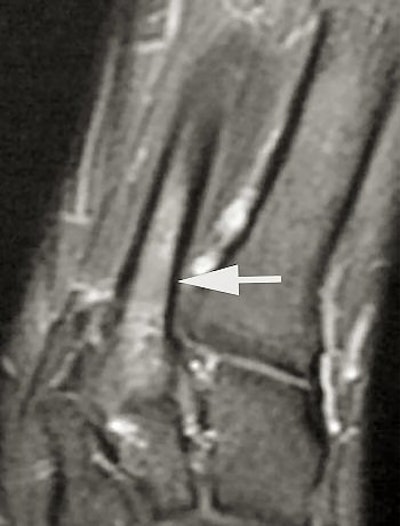

| Short axis image shows bone marrow edema at the base of the third metatarsal. |

The follow-up study was led by Dr. Nancy Major, associate professor of radiology at Duke University Medical Center's musculoskeletal division. Her study determined that MRI can effectively predict metatarsal stress fractures by depicting bone marrow edema (a precursor to fractures), thereby enabling the prevention of potential fractures with the use of orthotics.

In this study, 26 male basketball players from Duke and North Carolina Central University in Durham were imaged before and after their 2003 season. Although 19 of 52 feet showed abnormalities with MRI, only one player had complaints of a symptomatic midfoot. The use of an orthotic provided immediate relief, and the player did not subsequently develop stress fractures.

A player experiencing no symptoms, however, did develop a metatarsal stress fracture before he could be fitted for an orthotic ("The role of imaging in the feet in asymptomatic collegiate basketball players," RSNA meeting, December 2, 2004).